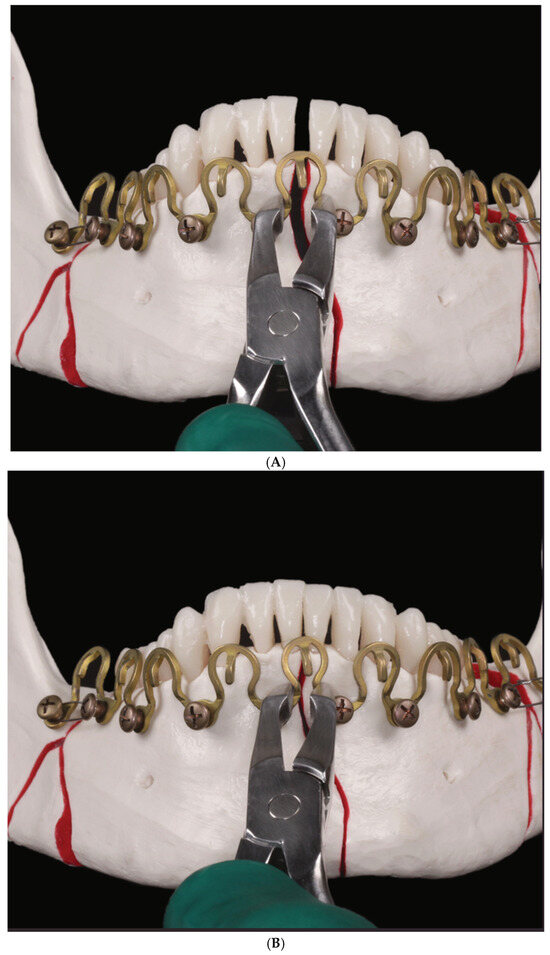

3.2. Matrix WaveTM Plate MMF System—Mode of Application